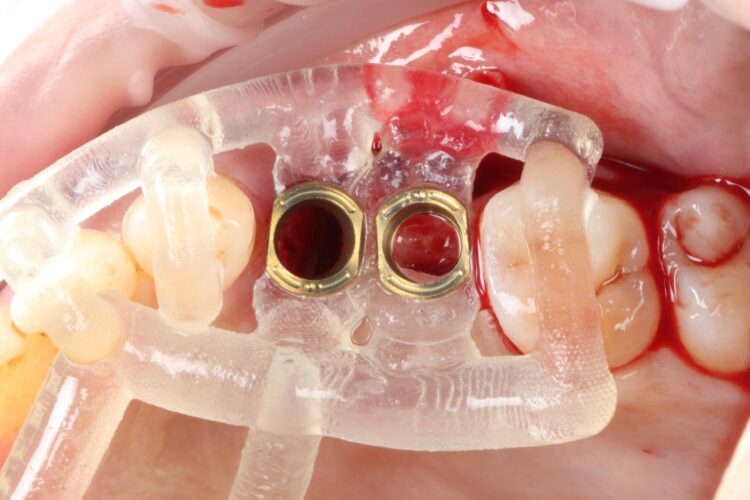

The surgical guide was then placed in the mouth and the manufacturer’s specific drilling sequence followed, increasing the osteotomy in size incrementally.

The CONELOG® Progressive implant 3.8mm is my go-to for premolar sites. The implant is versatile in its clinical application, suitable for use in healed ridges and fresh sockets, providing good stability for delayed and immediate implant placement protocols. It’s an all-in-one implant for me and I love using it.

Two 3.8mm diameter CONELOG® Progressive-Line implants were placed through the guide, following the plan precisely. The UL4 implant was longer (11mm) to ensure sufficient apical bone was engaged for primary stability, it was also positioned in the palatal root to ensure good engagement with the bone and better bone to implant contact. A sizable jump gap was noted between the implant and the buccal plate of around 5-6mm. From a biological perspective, the jump gap can be left because the ridge would heal to leave a sufficient buccal plate. However, the literature[iv] shows that grafting reduces the amount of bone resorption post implant placement, which was one of the reasons that augmentation was indicated in this case.

Another predetermined concern was the amount of remaining bone surrounding an implant after placement. There was less than 2mm of residual bone buccal to the UL5 site once the implant was placed. Alberto Monje et al. (2023) [v] showed that thin buccal bone at the implant site increases the risk of major dimensional changes, this can have direct implications on the aesthetics and functional outcomes.

Consequently, the bone was contour-augmented, using MinerOss® Blend (BioHorizons Camlog), which provides a good combination of cortical and cancellous bone for efficient bone turnover and also maintains graft stability in the healing phase. The graft was held in place with a collagen membrane stabilised using resorbable sutures. The custom healing abutment is then placed and torqued (10Ncm) into the UL4 implant before the wound is approximated and sutured using a non-resorbable 6-0 Prolene suture.